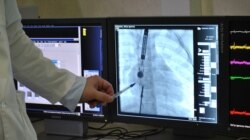

Оклюдер – це серцевий імплантат, який «закриває дірку» при дефекті перегородок серця. Він може розтягуватися в довгу трубочку і приймати форму парасольки розміром до 4 см. Його вводять через невеликі проколи на стегні, щоб він судинами рухався до серця. Після того, як оклюдер у вигляді складеної парасольки досягає отвору, його відкривають і фіксують. Із часом сполучна тканина проростає в нього, і оклюдер стає частиною серця.